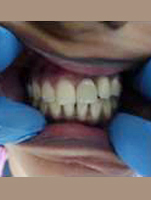

Single Tooth Implant

After Placement of Prosthesis